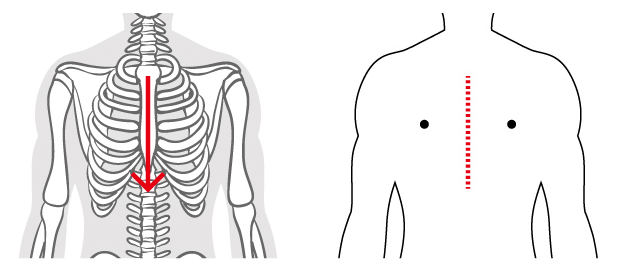

オフポンプ心拍動下冠動脈バイパス術

off pump coronary artery bypass grafting (OPCAB) (図1)

狭心症や心筋梗塞といった冠動脈の動脈硬化性病変に対する手術を冠動脈バイパス術といいます。現在でも多くの施設では人工心肺装置(図2)という大きな機械を心臓に装着してこの手術を行っていますが、機械による非生理的な血流であるため、脳血管の狭窄が強い患者さんや、腎機能障害や呼吸機能障害を有する重症の患者さんは合併病変が悪化することが危惧されていました。この問題を解決すべく、当院では2000年から人工心肺装置を用いずに、スタビライザー(図3)と言う器具を、冠動脈の走行する心臓表面に固定して拍動を抑えて血管縫合する<心拍動下冠動脈バイパス術>を導入しました。単独冠動脈バイパス手術の95%以上で行っております。

図1:心拍動下冠動脈バイパス術